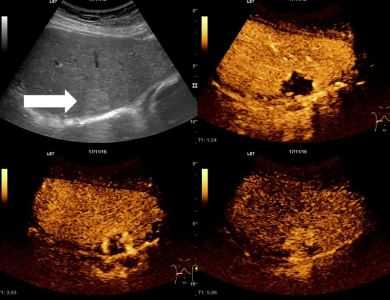

Данные, полученные при проведении УЗИ печени, интерпретируют с учетом нормальных показателей. В процессе интерпретации оценивают структуру печеночной паренхимы, размеры, контуры и эхогенность органа. При обнаружении очаговых изменений указывают их локализацию с учетом сегмента. При отсутствии патологических изменений по результатам УЗИ печень описывают как орган с гомогенной структурой и ровными контурами. Эхогенность печени ниже, чем у селезенки, и примерно равна эхогенности поджелудочной железы.

При проведении УЗИ печени могут определяться очень плотные участки (кальцификаты) и полости, заполненные жидкостью (кисты, абсцессы). Злокачественные неоплазии органа на УЗИ печени выглядят как участки необычного строения с неравномерной эхогенностью, неоднородной структурой и нечеткими границами. Плотность метастазов может быть как выше, так и ниже плотности ткани печени (в зависимости от плотности первичного новообразования), характерным признаком данной патологии является гипоэхогенный ободок вокруг патологического очага. Гемангиома при УЗИ печени представляет собой гиперэхогенное образование с четкими границами и акустической дорожкой, располагающееся рядом с крупными сосудами.

УЗИ печени используют в качестве ориентировочного метода, выявляющего изменения, характерные для различных заболеваний. Так, при циррозе печени на УЗИ определяется неоднородная структура паренхимы, бугристые края, повышенная эхогенность, изменение размеров долей, узлы регенерации, расширение портальной вены. При хроническом гепатите УЗИ печени выявляет неоднородную эхогенность в зонах воспаления, фиброза и интактных тканей, гепатомегалию, обедненный сосудистый рисунок. Кисты и абсцессы при УЗИ печени визуализируются как ограниченные округлые жидкостные образования.

Опухоли печени с доброкачественным ростом (гемангиомы) определяются в виде очагов уплотнений, отграниченных от нормальных тканей печени. Злокачественные первичные новообразования (гепатоцеллюлярная карцинома), а также метастазы при УЗИ печени выглядят как очаги уплотненной ткани. Любые объемные образования, выявляемые в ходе УЗИ печени, требуют уточняющей диагностики с помощью томографии (магнитно-резонансной или компьютерной). УЗИ печени и желчного пузыря позволяет определять наличие конкрементов в полости желчного пузыря при ЖКБ, утолщение стенок при холецистите, изменение тонуса стенок и перегиб шейки пузыря при дискинезии органов желчевыводящей системы.